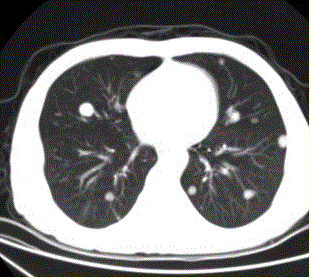

问题 患者男,45岁,因肝硬化、肝癌行肝移植术后6个月,咳嗽2周,来院复查。CR及CT影像如下图。 该例最可能的转移途径为

选项 A.经肺动脉 B.经肺动脉至淋巴管而后到肺外围 C.经纵隔淋巴结逆流到肺门淋巴结,再经肺内淋巴管到肺外周 D.经胸膜腔 E.经气道 F.经支气管动脉

答案 A